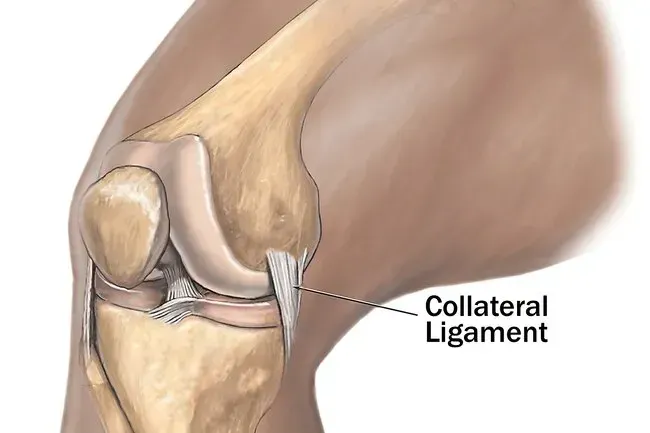

Bänder

Diese harten faserigen Dehnungskabel verbinden einen Knochen mit einem anderen. Sie helfen auch, Gelenke zusammen zu stärken und zu binden. Sie erlauben Bewegung in einige Richtungen, verhindern aber in anderen. Das Knie hat zwei Haupttypen. Kollaterale Bänder steuern die Bewegung für die seitliche Bewegung und verhindern, dass sich Ihr Knie nicht falsch bewegt. Kreuzbänder befinden sich im Gelenk und helfen ihm, sich vorwärts und rückwärts zu bewegen.

Kollateralbandriss

Dies geschieht normalerweise auf eine von zwei Arten: Entweder trifft etwas Außensend Ihres Knies, was das mediale Kollateralband oder etwas auf das Innere des Knies schädigt, was das laterale Kollateralband verletzt (dies ist weniger häufig). Sie werden Schmerzen und Schwellungen haben. Das Gelenk kann sich schwach oder instabil anfühlen.

Kollateralbandbehandlung

Diese Verletzungen erfordern selten eine Operation. Eis die Gegend für 15 bis 20 Minuten auf einmal mit mindestens einer Stunde zwischen den Sitzungen. Ihr Arzt kann Ihnen helfen, Ihr Knie zu sammeln, um die Bewegung zu vermeiden, die die Verletzung überhaupt verursacht hat. Möglicherweise müssen Sie auch Ihre täglichen Routine- und Übungsgewohnheiten ändern. Möglicherweise müssen Sie Krücken verwenden, um die Verbindung für eine Weile abzunehmen. Physiotherapie könnte auch helfen.